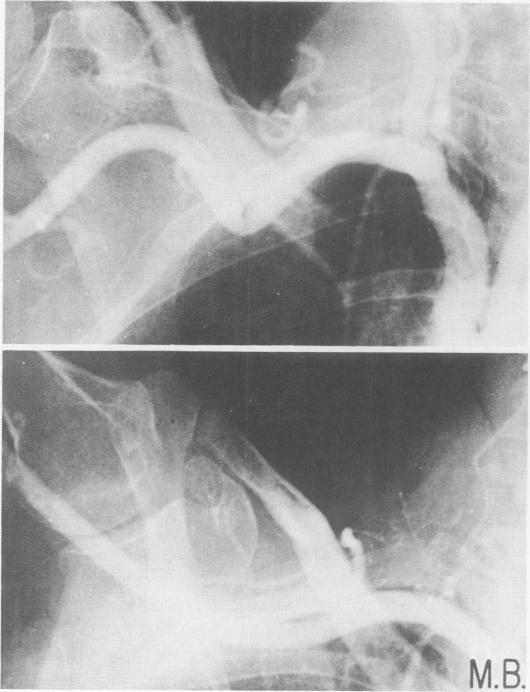

胸廓出口综合征的管理

Management of thoracic outlet syndrome.

This overall management program for thoracic outlet compression syndrome is based upon experience with 153 extremities in 149 patients and the results of others. The following conclusions are documented and discussed. 1) Diagnosis is based chiefly upon history; physical signs are inconstant and often absent. 2) Major vascular problems are unusual; angiography is not always necessary. 3) Electromyography is not always critical but does aid in diagnosis of carpal tunnel syndrome. 4) Non-operative treatment relieves most patients; operative decompression is indicated for a minority. 5) Transxillary first rib resection, with removal of cervical rib is the best operation. 6) Carpal tunnel decompression should be done concomitantly when needed. 7) Operation is relatively safe.

摘要

这个胸廓出口综合征的整体管理方案是基于对149例患者的153个肢体的经验以及其他研究结果制定的。以下结论得到了记录和讨论。1)诊断主要基于病史;体征不稳定且常不存在。2)主要血管问题不常见;血管造影并非总是必要的。3)肌电图并非总是关键的,但有助于诊断腕管综合征。4)非手术治疗可使大多数患者缓解;少数患者需要手术减压。5)经腋路第一肋切除术并切除颈肋是最佳手术方式。6)必要时应同时进行腕管减压术。7)手术相对安全。